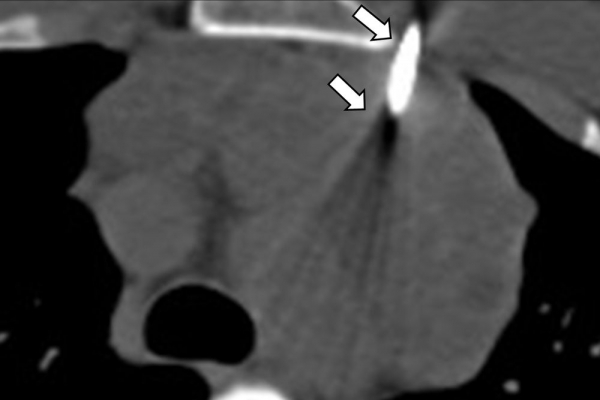

Η διαδερμική βιοψία είναι μία ελάχιστα επεμβατική μέθοδος λήψης υλικού από τον όγκο για κυτταρολογική και ιστολογική εξέταση, από εστιακές αλλοιώσεις του ήπατος, πνεύμονα, νεφρού κλπ. Συστήνεται από τον κλινικό ιατρό ανάλογα με το είδος και το μέγεθος της βλάβης και πραγματοποιείται με ασφάλεια από επεμβατικό ακτινολόγο με την καθοδήγηση αξονικού τομογράφου ή υπερήχων. Στη σύγχρονη ογκολογική θεραπεία όπου γίνεται προσπάθεια καταπολέμησης του καρκίνου σε μοριακό επίπεδο κρίνεται αναγκαία η ακριβής ιστολογική ταυτοποίηση του όγκου ώστε να εφαρμοσθεί εξατομικευμένη θεραπεία για το βέλτιστο αποτέλεσμα. Οι κατευθυνόμενες βιοψίες στοχευουν στο να παρέχουν στον κλινικό ογκολόγο το απαραίτο ιστοπαθολογικό υλικό που θα του επιτρέψει να εφαρμόσει την κατάλληλη θεραπεία για τον ογκολογικό ασθενή.